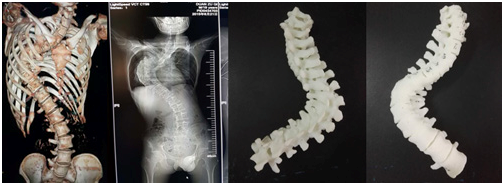

利用3D打印技术给脊柱侧弯患者制作的模型

会上,SICOT中国部数字骨科学会主任委员裴国献教授对数字骨科现状、存在问题及未来对策进行了淋漓尽致的分析,并对我省的数字骨科发展和3D打印技术的应用表示赞许。会议对临床医学院/附属医院骨三科朱述浪主任团队在九江地区率先利用3D打印技术为脊柱侧弯患者制作脊柱模型给予高度肯定。该次手术中,术前直观、准确地掌握脊柱畸形的具体病变情况,制定手术计划,术中与模型对照.判断畸形椎体椎弓根的位置和方向;患者手术过程顺利,矫形和内固定满意,未出现神经、血管损伤等并发症。

对于一些复杂骨折和畸形,单纯凭借CT或MRI等影像学资料难以对局部解剖结构形成形象、直观的认识,手术难度和风险较大。3D打印骨骼模型将真实的骨骼结构呈现在眼前,可以更加直观地了解病变的严重程度,分析导致病变的原因和机制,有助于疾病的分型及诊断,同时还可用来计划和模拟手术。这是3D打印技术在骨科领域应用研究的重点内容之一,国内外已经有较多学者在这方面做了大量研究工作。